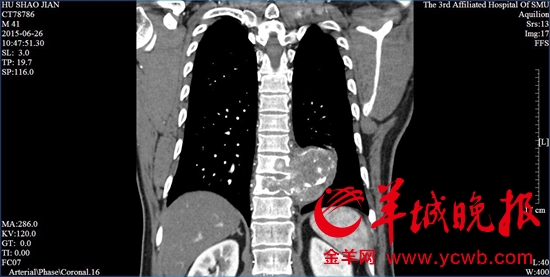

一位患者的脊柱已被腫瘤包圍。(圖片來源:金羊網)